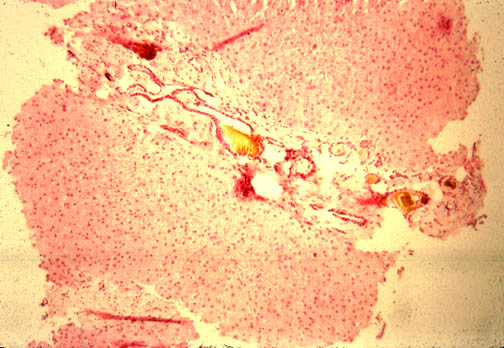

| In this case you see dilated ducts and portal fibrosis. There is a combination of congenital ductal dilatation (Caroli' syndrome) and congenital hepatic fibrosis. |